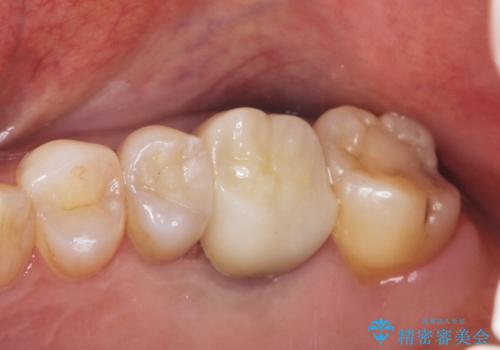

金属をセラミックにしたい、根管治療も行ったケース

奥歯の目立つ銀歯を白くしたい